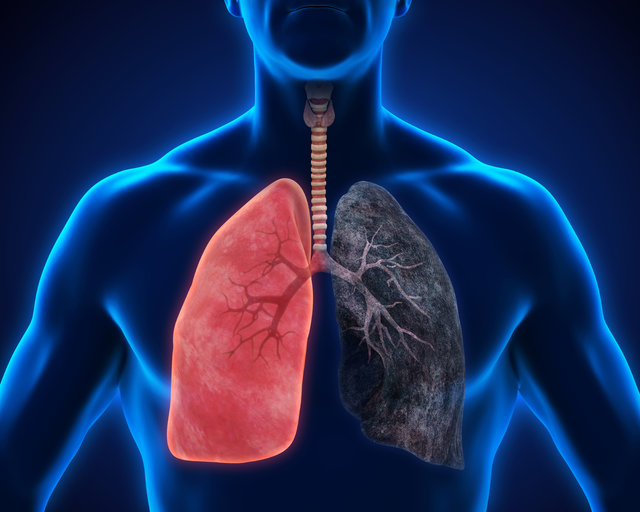

Sigara içmek akciğer kanseri için bir numaralı risk faktörüdür. Pipo ve puro benzeri tütün ürünlerinin kullanılması ve ikinci el sigara dumanına maruz kalmak akciğer kanseri riskini artırmaktadır.

Sigara içenler, sigara içmeyenlere göre 15 ila 30 kat daha fazla akciğer kanserine yakalanmaktadır. Günde birkaç sigara içilmesi bile akciğer kanseri riskini artırır. Her yaşta sigarayı bırakmak akciğer kanserinden korunmak için en önemli adımdır.